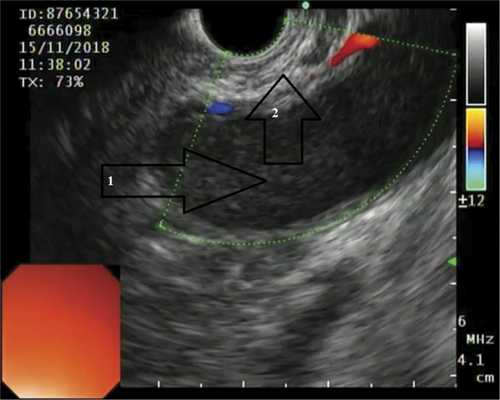

ПК локализовались в теле ПЖ у 7 (30,4%) пациентов, в хвосте ПЖ — у 7 (30,4%), в головке ПЖ — у 6 (26,2%) (рис. 1). Рис. 1. Псевдокиста головки поджелудочной железы (изображение при ультразвуковом исследовании). Стрелками указаны полость псевдокисты (1), бессосудистая зона (2). The arrows indicate pseudocyst cavity (1), avascular zone (2). У 3 (1%) больных имело место сочетанное расположение ПК в головке и теле ПЖ.

Пластиковые стенты применяли при наличии «зрелой» фиброзной капсулы толщиной от 3 до 9 мм и однородном содержимом кисты. Металлические саморасширяющиеся стенты устанавливали в отсутствие капсулы, при инфицированном содержимом и наличии секвестров (рис. 2). Рис. 2. Состояние после цистогастростомии. а — саморасширяющийся стент в просвете инфицированной кисты указан стрелкой (изображение получено при эндоскопической ультрасонографии); б — саморасширяющийся стент в просвете инфицированной кисты указан стрелкой 2 (по данным рентгенографии); в — пластиковый стент в просвете неинфицированной кисты указан стрелкой (изображение получено при эндоскопической ультрасонографии); г — пластиковый стент в просвете неинфицированной кисты указан стрелками (по данным рентгенографии). a — self-expanding stent inside infected cyst is indicated by the arrow 2 (us); b — self-expanding stent inside infected cyst is indicated by the arrow 2 (X-ray); c — plastic stent inside sterile cyst is indicated by the arrow (us); d — plastic stent inside sterile cyst is indicated by the arrows (X-ray).